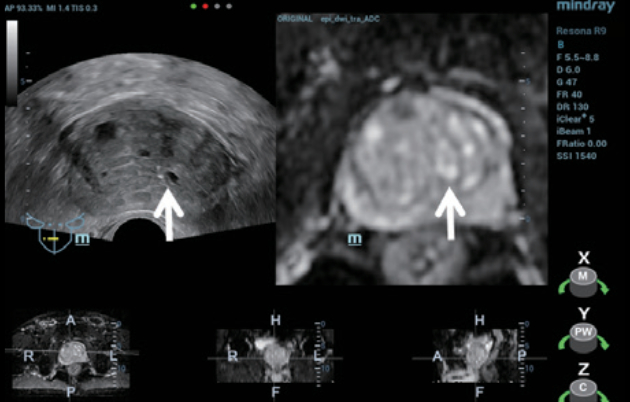

TRUS finding (figure 1):?

- Prostatic hyperplasia with calcifications and small prostatic cysts.

- Heterogeneous prostatic echotexture with no discrete lesion identified.

Step 1: The appropriate MRI sequence (Figure 2) was selected and the dataset imported onto the Resona 9 and into the live ultrasound exam.

Step 2:?Using MindrayŌĆÖs iFusion software, the TRUS and MRI images were aligned and fused (Figure 3) and the target was labeled (Figure 4).